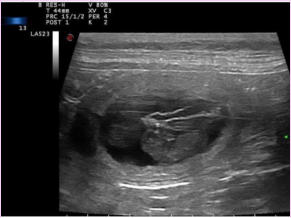

Ich werde Mama, der heutige Ultraschall war positiv.